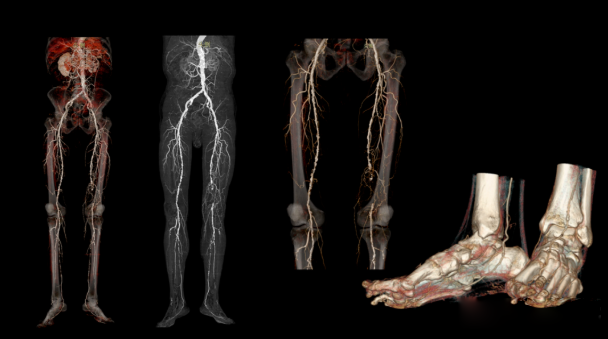

1、CT血管造影:

血管造影可以评估血管及脏器功能,准确判断血管瘤、血管畸形、血管狭窄,肿瘤供血、出血、栓塞、等情况,为治疗提供有效帮助。